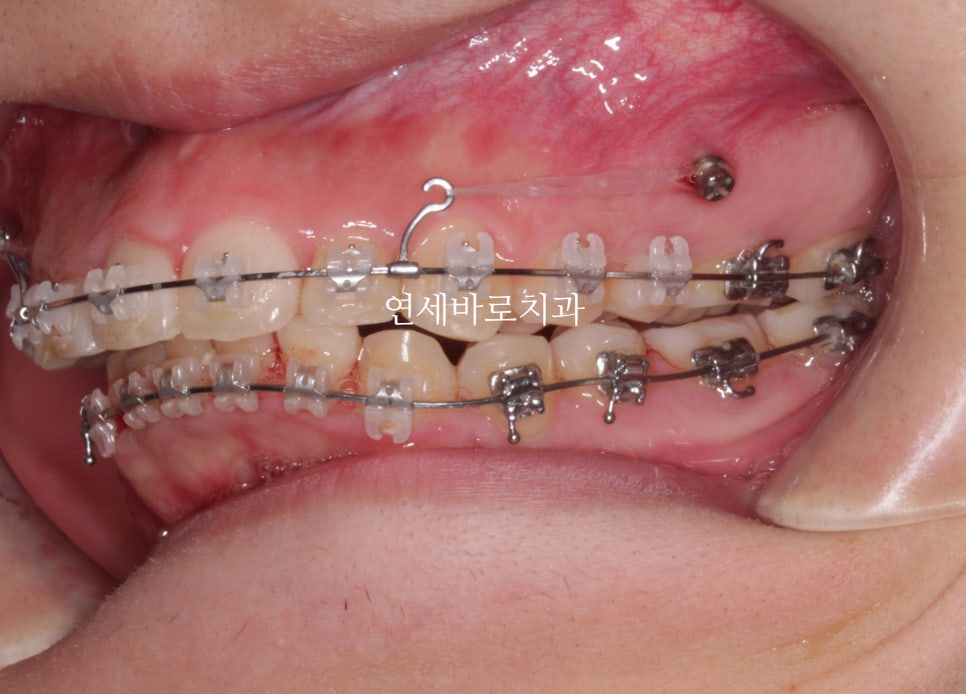

어느정도 준비를 하는 배열의 시간이 지나가고 #미니스크류 를 식립했습니다.

환자분의 골격상태 등을 고려하여 진단했고, 미니스크류를 많이 심진 않았습니다.

위쪽은 2개 심고 치료를 마무리 했습니다.

아래쪽은 중심선을 맞추기 위해 편측으로 1개만 식립.

시간이 오래 지났지만 계속 당기기만 합니다.

당기면 들어갑니다.

뒤에 공간만 있으면 뒤로 갑니다.

공간은 CT등을 통해 지속적인 확인을 하면서 진행합니다.

어금니 관계를 보면 1:1 로 만나던 치아가 사이사이 지그재그 들어가는 것이 보이죠?

약 5mm정도 후방이동 된 것으로 보입니다.